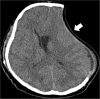

Malignant stroke occurs in a subgroup of patients suffering from ischemic cerebral infarction and is characterized by neurological deterioration due to progressive edema, raised intracranial pressure, and cerebral herniation. Decompressive craniectomy (DC) is a surgical technique aiming to open the "closed box" represented by the non-expandable skull in cases of refractory intracranial hypertension. It is a valuable modality in the armamentarium to treat patients with malignant stroke: the life-saving effect has been proven for both supratentorial and infratentorial DC in virtually all age groups. This leaves physicians with the difficult task to decide who will require early or preemptive surgery and who might benefit from postponing surgery until clear evidence of deterioration evolves. Together with the patient's relatives, physicians also have to ascertain whether the patient will have acceptable disability and quality of life in his or her presumed perception, based on preoperative predictions. This complex decision-making process can only be managed with interdisciplinary efforts and should be supported by continued research in the age of personalized medicine.